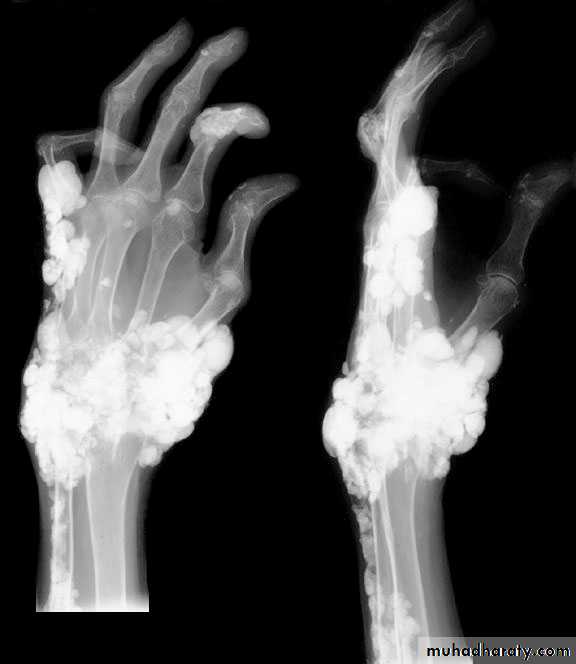

Primary hyperparathyroidism(Radiological features)

Characteristic changes on plane X ray are:

Demineralization, subperiosteal erosion and resorption of terminal phalanges

Soft tissue calcification affecting arterial walls, hands or cornea